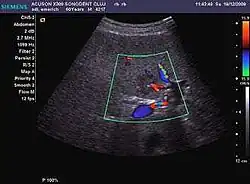

HCC appearance on 2D ultrasound is that of a solid tumor, with imprecise delineation, with heterogeneous structure, uni- or multilocular (encephaloid form). An "infiltrative" type is also described which is difficult to discriminate from liver nodular reconstruction in cirrhosis. Typically HCC invades liver vessels, primarily the portal veins but also the hepatic veins . Doppler examination detects a high speed arterial flow and low impedance index (correlated with described changes in tumor angiogenesis). The spatial distribution of the vessels is irregular, disordered. CEUS examination shows hyperenhancement of the lesion during the arterial phase. During the portal venous phase there is a specific "wash out" of ultrasound contrast agent (UCA) and the tumor appears hypoechoic during the late phase. Poorly differentiated tumors may have a stronger wash out leading to an isoechoic appearance to the liver parenchyma during portal venous phase. This appearance was found in approx. 30% of cases. The described changes have diagnostic value in liver nodules larger than 2 cm.

Spectral Doppler characteristics of early HCC overlap those of the dysplastic nodule, as they are represented by the presence of portal venous signal type or arterial type with normal RI (well differentiated HCC) or increased RI (moderately or poorly differentiated HCC). The CFM exploration identifies a chaotic vessels pattern.